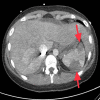

Figure 4

Figure 4. Multiple peripheral wedge-shaped infarcts in the spleen